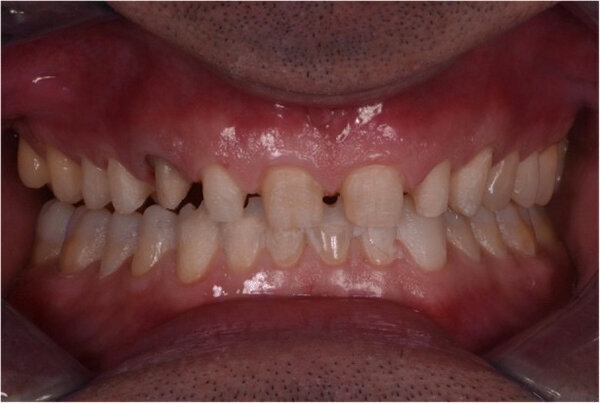

En 2015, un paciente de 47 años se quejó de dolor en la ATM. Teníamos también una solicitud estética, ya que parte de la carilla de uno de los incisivos centrales superiores se había roto (Figs. 1-3). El análisis clínico y radiográfico (Fig. 4) ocasionó una pérdida de altura de la mordida y; una sustancia dental debida a un bruxismo.

Fig. 1. Fotografías intraorales iniciales, vista frontal (A), vista oclusal del maxilar (B) y vista oclusal de la mandíbula (C).